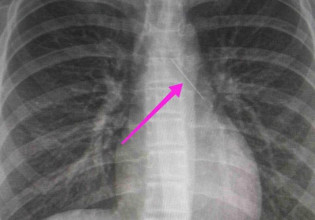

Από την απεικονιστική διερεύνηση που πραγματοποιήθηκε με ακτινογραφία θώρακος αρχικά και ακολούθως με αξονική τομογραφία θώρακος, διαπιστώθηκε η ύπαρξη αιχμηρού μεταλλικού ξένου σώματος στην αναπνευστική οδό (αριστερός κύριος βρόγχος) και όχι στην πεπτική οδό.

Η ανήλικη υπεβλήθη σε βρογχοσκόπηση και διαπιστώθηκε η μετακίνηση και ενσφήνωση της καρφίτσας στον δεξιό κύριο βρόγχο. Μετά οπό εργώδεις προσπάθειες ολοκληρώθηκε με επιτυχία η αφαίρεσή της.

Το κορίτσι μεταφέρθηκε αμέσως στο νοσοκομείο και οι γιατροί εντόπισαν αρχικά την καρφίτσα στον αριστερό βρόγχο, στον αυλό που οδηγεί στον πνεύμονα. Όταν όμως έγινε η βρογχοσκόπηση, βρέθηκε στον άλλον βρόγχο.